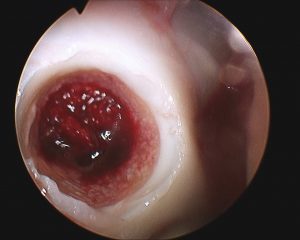

• Entnahme des oder der Defektzylinder (weiß) Donor wichtig im korrekten Winkel entnehmen!

• Entnahme des oder der Zylinder (blau) Recipience